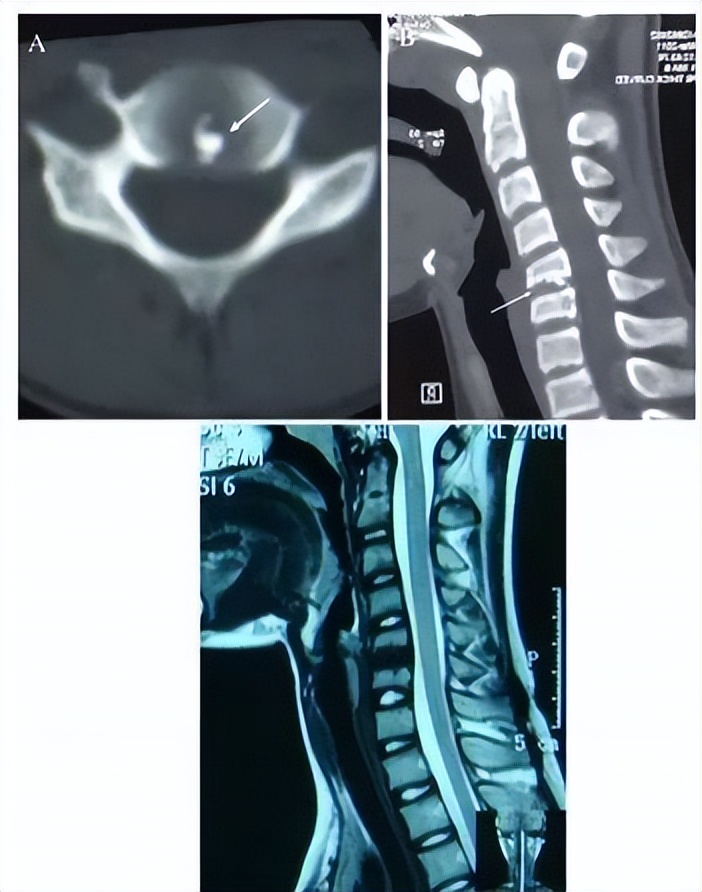

一位88岁女性患者,主诉急性颈痛伴发热2个月入院。体温波动在38-39.3℃,无视力模糊,无神经及脊髓压迫征象。颈椎CT+矢状位重建显示寰椎横韧带的曲线状钙化(图A,箭头所示),线性钙化(图B,箭头所示),以及齿状突周围的冠状钙沉积(图C,箭头所示)。给予短期非甾体抗炎药和泼尼松龙(15mg/d)后,其上述症状完全缓解。同时,作者指出这类疾病通常不需要长期用药。

颈椎CT平扫示齿状突后侧寰椎横韧带弧形钙化(左图箭头)和竖直线样钙化(右图箭头)。依据患者病史、体征及辅助检查,齿状突加冠综合征可基本诊断。入院后给予氯诺昔康 8 mg静脉滴注每日2次,地塞米松起始量10 mg静脉滴注每日1次,3日后改为5mg/d。连续治疗5 d后,患者入院时症状明显缓解,复查白细胞、红细胞沉降率、超敏C反应蛋白均恢复正常。随访半年,未有颈痛伴发热症状出现。